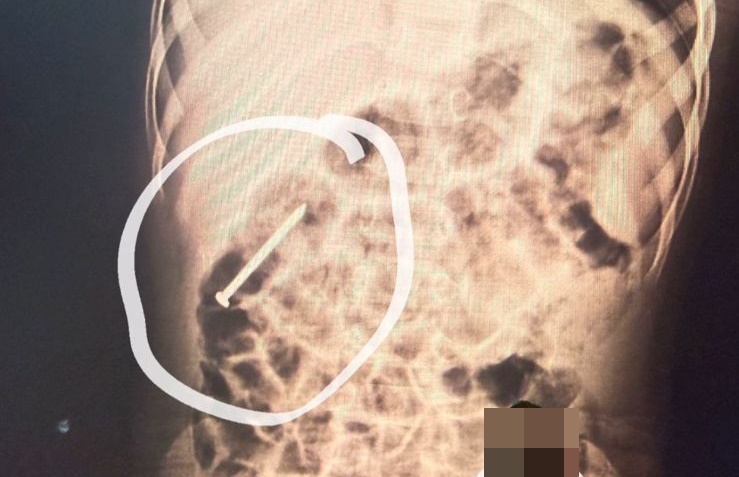

Um menino de 2 anos do município de Ipixuna está internado no Hospital do Juruá após engolir um prego há cerca de seis dias.

Segundo os profissionais de saúde, o objeto está avançando pelo aparelho digestivo de forma natural. Por precaução, a criança permanece hospitalizada para acompanhamento médico, enquanto se aguarda que o material seja eliminado sem a necessidade de procedimentos.